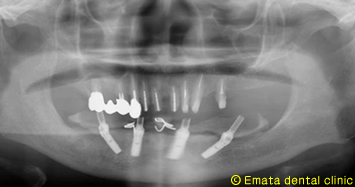

奥歯の骨が少ないです。

CTでシュミレーションを行いました。奥歯には骨がありませんが、前歯の骨がありますので神経までの距離が近いですが、All-on-4の適応症です。

下顎神経を避けて、4本のインプラントが綺麗に埋入されています。

ポルトガル 「マロ・クリニック」での研修の成果です。